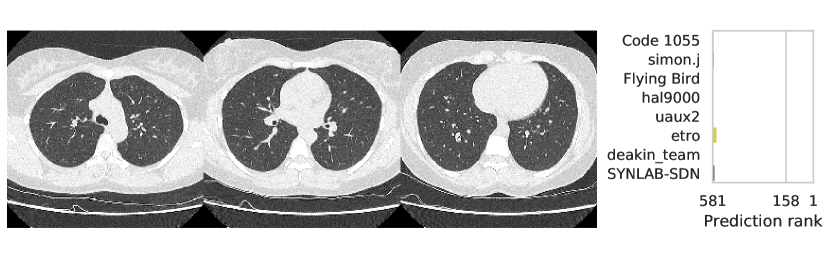

3.2.3 Performance

Table 1 shows the AUC on test set B for COVID-19 presence and severity of the teams that submitted to the Final phase. Figure 4 shows Receiving Operating Characteristics (ROC) curves of the six successful Final phase submissions for discriminating between severe and non-severe COVID-19 subjects from test set B. Figures 5 and 6 show how the finalists ranked the subjects from test set B with severe and non-severe COVID-19 respectively for presence of severe COVID-19. Figures 7 and 8 highlight some individual cases from test set B. During the original STOIC project [67], a logistic regression model was developed to predict severe COVID-19 using clinical variables and CT annotations by radiologists. It was developed and evaluated using the patients from the STOIC who were COVID-19 positive for both RT-PCR and CT, and had unenhanced CT. Of these 4238 patients, 1000 developed severe COVID-19. Revel and colleagues 6 reported an AUC for this model of 0.69 (CI: 0.67-0.71). To compare this model against the results from STOIC2021, an ensemble of the top three solutions for severe COVID-19 prediction was evaluated on the 367 patients from test set B who were COVID-19 positive for both RT-PCR and CT, and had unenhanced CT. 97 of these patients developed severe COVID-19. The top three ensemble achieved an AUC of 0.783 (CI: 0.706-0.848).